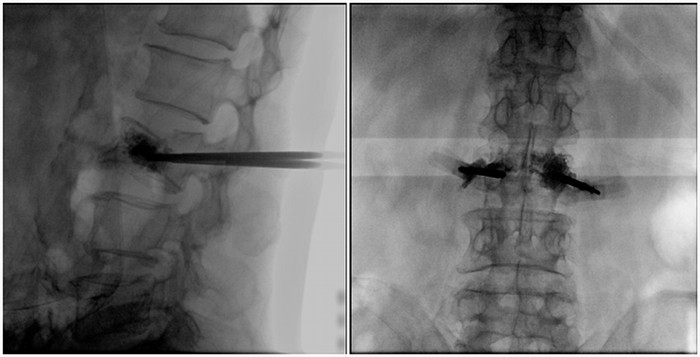

普爱医疗大平板一体式移动C臂采用30cm×30cm的平板探测器,能在手术过程中,为医生提供更广阔的视野范围,带给医生更全面的影像信息。在进行脊柱类手术时,一次曝光即可呈现全节段腰椎,避免因为呈像不全而导致重复曝光,不仅提高了手术效率,而且避免医生吸收过量的辐射。